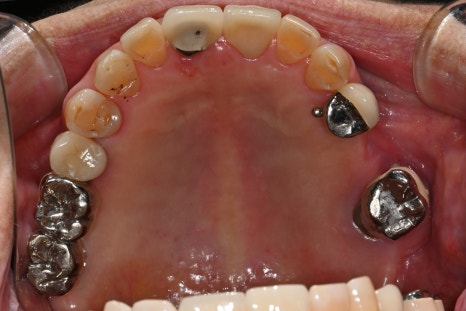

✅ 치료 전 사진

왼쪽 사진: 처음 내원하셨을 때 촬영한 파노라마 엑스레이입니다.

기존 임플란트 주변 어금니 여러 개에서 염증과 흔들림이 보였고, 전체적으로 저작 기능 저하와 심미적인 불편함이 있었습니다.

오른쪽 사진: 환자분의 앞니 구강 내 사진입니다.

앞니는 깨지고 오래된 보철물도 있어, 심미성과 기능 회복이 함께 필요한 상태였습니다.